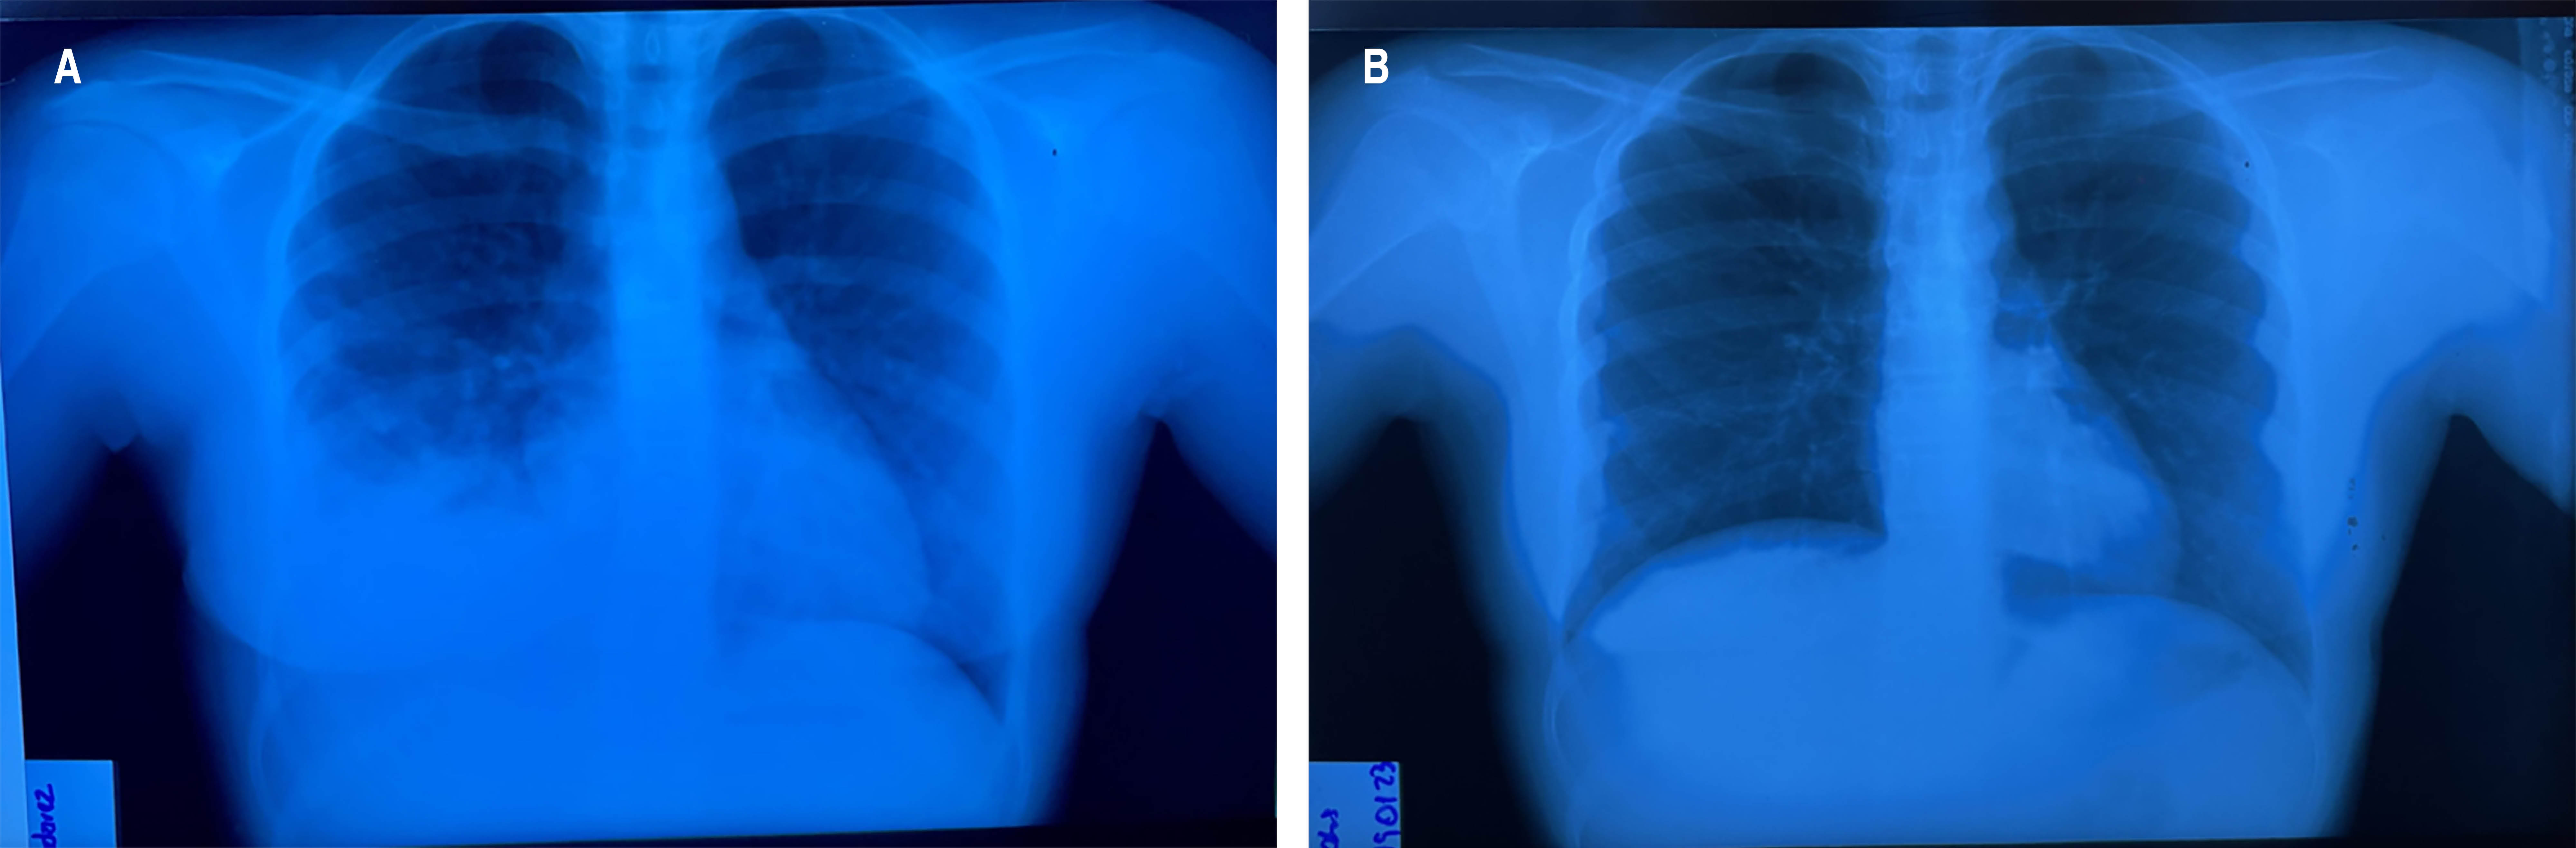

Figure 1